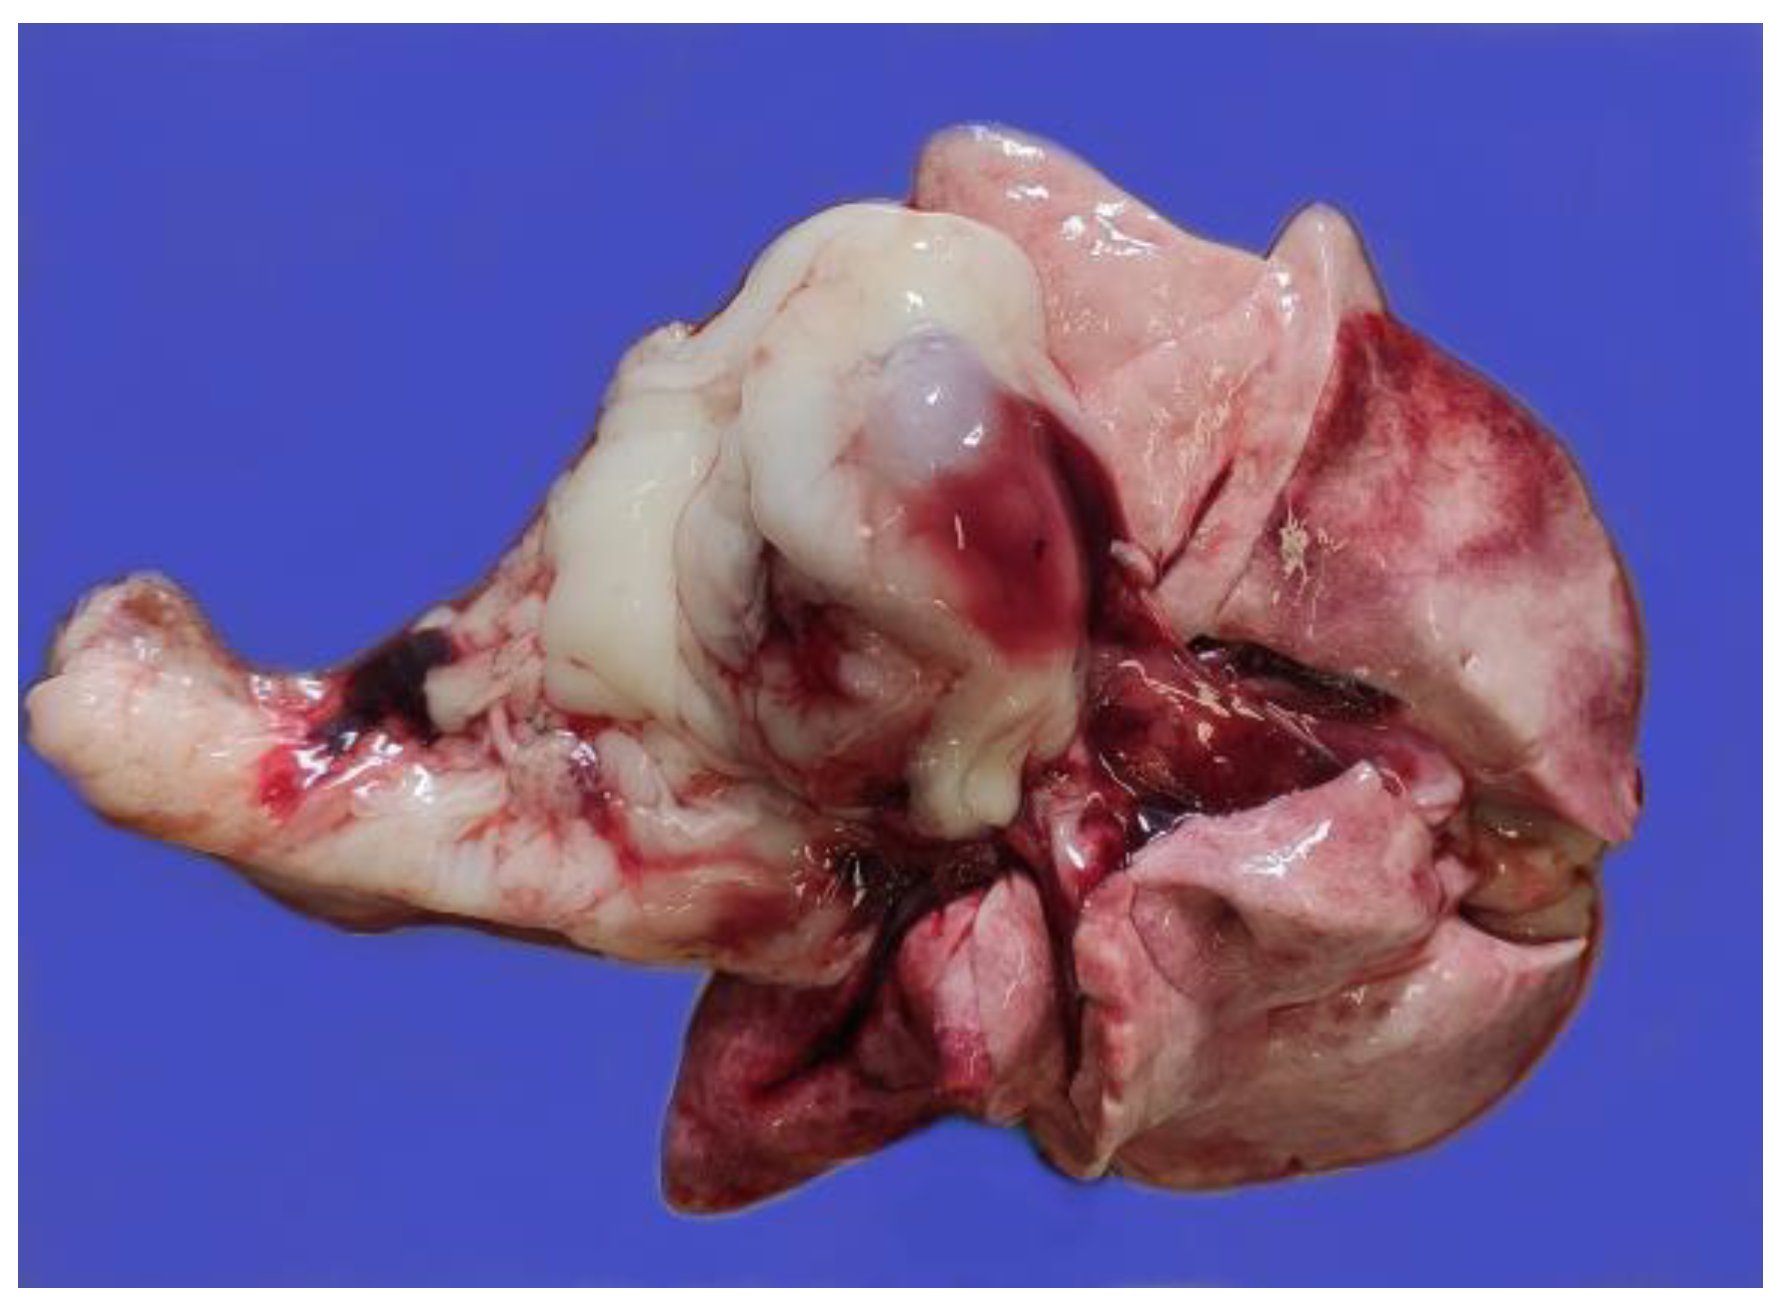

2.1. Anatomopathological Examination